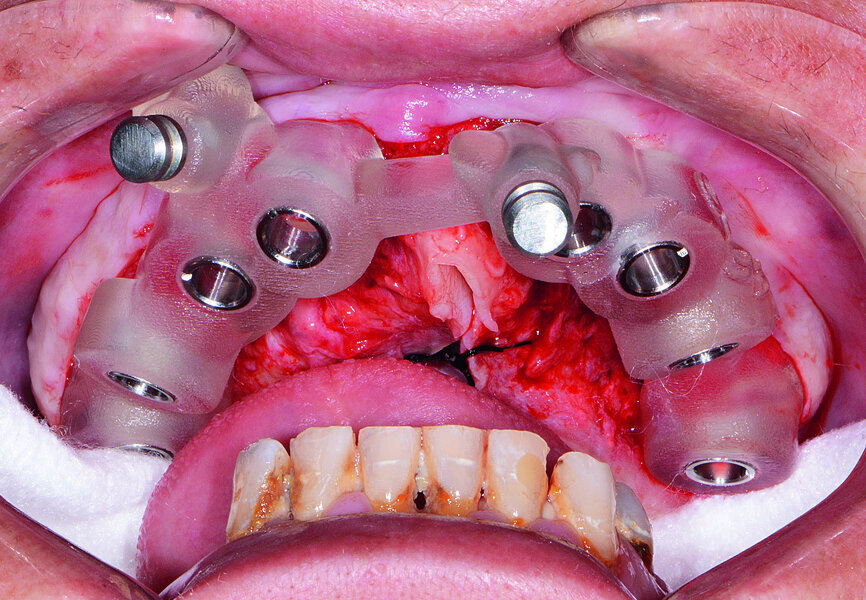

Fig. 14: Mandibular surgical guide stabilised.

Next, the patient’s untreatable mandibular teeth (Fig. 13) were extracted using the Physics Forceps (GoldenDent), a flap was reflected, and an alveoloplasty was performed. A bone-supported guide was seated in order to control the location and angulation of the implant osteotomies (Fig. 14). As the Hahn Tapered Implants were threaded into place, their deep, sharp threads engaged the walls of the socket sites and helped maintain proper position toward the lingual aspect. Because of anticipated tissue swelling as a result of the bone levelling procedure, 5 mm high healing abutments were connected to the implants in the lower arch (Fig. 15). The immediate dentures were soft-relined with Mucopren (Kettenbach) to seat over the Hahn Tapered Implant Healing Abutments, the hourglass shape and undercuts of which provided a degree of retention that enhanced dental function for the patient during healing (Fig. 16).